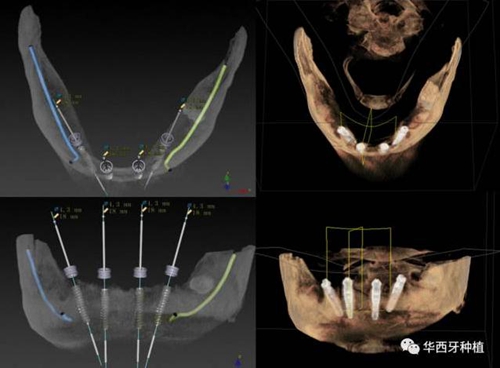

對于傳統(tǒng)的all-on-four術式,吳教授加入了微創(chuàng)的指導思想,設計時同樣加入數(shù)字化三維重建與修復一體化設計,增加了手術的可控性,同時極大減輕了患者的創(chuàng)傷程度,縮短了修復周期。

吳教授提到了使用數(shù)字化建模與導板的聯(lián)合應用,不僅可以從設計上降低修復難度,便于在修復為導向的設計中種植體方向的確定,同時可以加入微創(chuàng)的手術方法,減輕術中創(chuàng)傷。